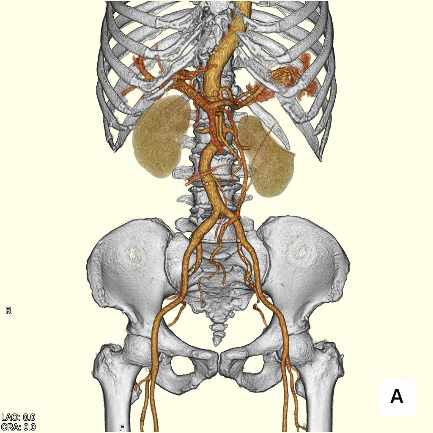

【CT(computed tomography)】

管球(ドーナツ状の部分にあるX線を出す機械)がX線を出しながら体の周りを回転し、人体を透過したX線をコンピューター処理して画像化します。短時間で広い範囲を撮影でき、様々な方向からの画像や3Dを作成します。